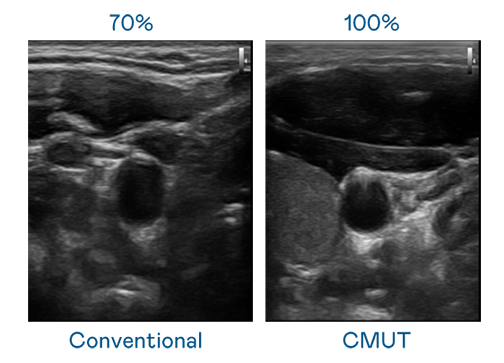

CMUT 技术是一种用电容式微机电元件来产生超音波讯号的技术。与传统 PZT 压电式技术相比,CMUT 频宽增加 30%,更宽频的超音波讯号让影像解析度大幅提升,是实现高影像品质医疗超音波扫描、促进精准医疗发展的关键技术。

超音波影像的解析度高低,首先取决于探头能发出的讯号频宽。利来w66国际 CMUT 可提供高清晰的超音波讯号,提供高频宽、高灵敏度、影像纹理细节更高的超音波影像,协助医护人员缩短影像判读时间及利用精准的医疗影像进行诊断。